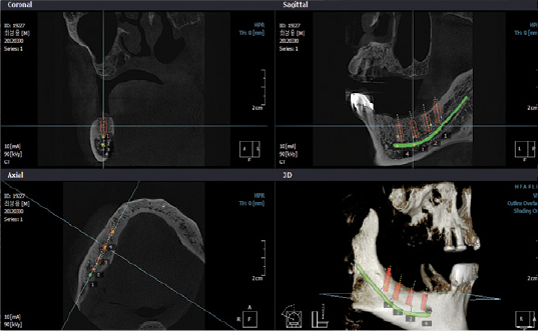

• Pianificazione terapeutica mediante trattamenti implantari

• Programmazione di chirurgia implatare guidata

• Follow up di trattamenti implantari

• Individuazione di fistole, sinusite mascellare odontogena e processi infiammatori periradicolari

• Studio anomalie della dentizione (anomalie di posizione dei denti del giudizio o dei canini)

• Studio di aree di sclerosi e disomogeneità ossea dei mascellari

• Studio in 3D delle articolazioni temporo-mandibolari

• Studio in 3D dei seni mascellari